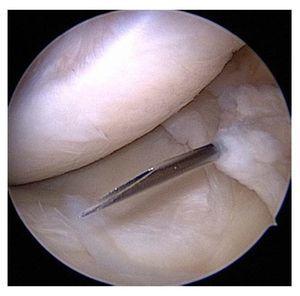

Fig. 19 8 Si la angulación del alambre es ligeramente errónea, la posición del túnel se puede corregir paso a paso realizando una perforación excéntrica hacia la posición deseada. Para ello debe perforarse primero la cavidad correcta con una broca delgada (a, b). A continuación se desplaza el alambre excéntricamente dentro del túnel y se prosigue con la perforación (c, d).